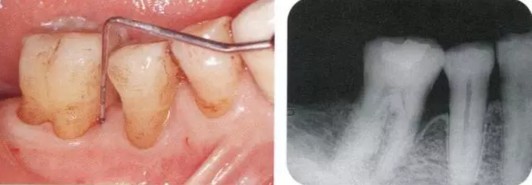

2222222222.png

40歲,女性。來院主訴為牙齦出血,牙體晃動(dòng)。患者不吸煙,因此沒有全身性問題。有明顯的牙周炎,發(fā)生了牙體移動(dòng),前牙區(qū)前突。下頜右側(cè)磨牙缺失,醫(yī)生認(rèn)為有必要進(jìn)行包括牙周修復(fù)、正畸治療、種植治療等在內(nèi)的綜合性治療。

22222222222222.png

▲圖19-2,3

上下頜咬合面照。

22222222222222222222222222.png

▲圖19-4

X光片。牙槽骨明顯缺失。